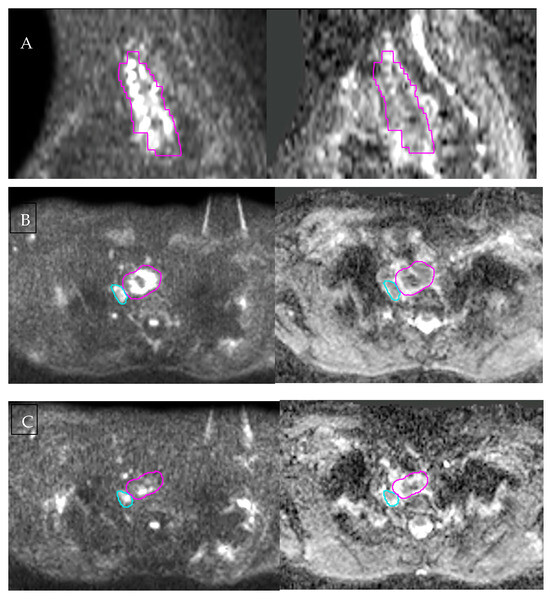

Several complementary MRI sequences contribute to improved tumour visualisation for radiotherapy planning, with the T2-weighted sequence defining wall anatomy and diffusion-weighted imaging assisting in distinguishing tumour from surrounding oedema or inflammation. An example of diffusion-restricted tumour extent on baseline DWI is shown in Figure 2A.

Figure 2.

Diffusion-weighted MRI for baseline tumour characterisation and early treatment-related change. (A) Baseline sagittal DWI and corresponding ADC map illustrate the craniocaudal extent of the primary oesophageal tumour. (B) Baseline axial DWI and ADC demonstrate marked diffusion restriction within the tumour, with the gross tumour volume (pink) and a suspicious lymph node (blue) contoured. (C) Mid-treatment axial DWI and ADC acquired after 13 fractions of chemoradiotherapy show reduced diffusion restriction and increased ADC values. All images were acquired on the authors’ institutional MR-Linac and are presented for illustration only. Figure 1 and Figure 2 are derived from the same imaging dataset.

DWI measures the Brownian motion of water molecules within tissue and provides indirect information on tissue cellularity and microstructure. Malignant tissues typically show restricted diffusion due to high cellular density and reduced extracellular space, resulting in high signal intensity on high-b-value DIW and low values on corresponding ADC maps. At baseline, multiple studies have demonstrated that lower ADC values are associated with more-advanced disease stage, poorer differentiation, and an increased likelihood of nodal involvement [43,44]. Beyond baseline tumour characterisation, serial ADC measurements during treatment are promising biomarkers for early treatment response. During treatment, diffusion restriction diminishes, and ADC values rise due to tumour necrosis and decreased cellularity. This temporal change is illustrated in Figure 2, demonstrating changes from baseline and mid-treatment imaging.